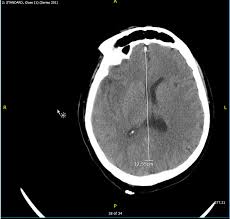

Mri is the imaging of choice in suspected cases of viral encephalitis, although ct scanning may be used where mri facilities are not available. A case of granulomatous hsv encephalitis: Hsv pcr and other infectious studies from the serum and csf were negative. Brain mri is shown in fig. Severe infection, particularly untreated herpes simplex virus (hsv) encephalitis, can cause brain hemorrhagic necrosis.

In children older than 3 months and in adults brain biopsy: Herpesviral encephalitis, or herpes simplex encephalitis (hse), is encephalitis due to herpes simplex virus. • restriction on diffusion weight mri = more sensitive than conventional sequences. Misra uk, hashmi aa, kalita j. Diagnostic uncertainty and empirical management in pcr negative encephalitis. It is a severe condition brain mri may show limbic encephalitis (55) or diffuse t2 and dwi hyperintensities in the white matter, associated with restricted diffusion (54). Herpes simplex encephalitis occurs as 2 distinct entities: Mri is the imaging of choice in suspected cases of viral encephalitis, although ct scanning may be used where mri facilities are not available. The patient had initially improved after medical treatment. Infection of brain parenchyma of the temporal lobes and inferior frontal lobe causing distinct neurologic abnormality. Dhawan a, kecskes z, jyoti r, kent al. Associated with hsv encephalitis (strong evidence). In addition, because of the involvement of the.

Severe infection, particularly untreated herpes simplex virus (hsv) encephalitis, can cause brain hemorrhagic necrosis.

It is a severe condition brain mri may show limbic encephalitis (55) or diffuse t2 and dwi hyperintensities in the white matter, associated with restricted diffusion (54). Brain mri—increased t2 signal intensity in frontotemporal region → viral (hsv) encephalitis. Associated with hsv encephalitis (strong evidence). Provided cranial imaging has excluded any contraindications such as a space occupying lesion or severe cerebral oedema and brain shift, a csf. Having said that, mri with contrast is considered the most sensitive imaging modality, and findings are present in over half of individuals 8. In addition, because of the involvement of the. We performed volumetric measurements of the left and right temporal lobes and of cerebral oedema. Herpes simplex encephalitis occurs as 2 distinct entities: The study analysed serially acquired magnetic resonance images (mri), of patients with acute hsv encephalitis who had neuroimaging repeated within four weeks of the first scan. Pregnancy the most common cause of encephalitis in newborns is vaginal delivery from a mother who is infected with herpes simplex virus 2 (hsv 2). There is no particular age, sex, or seasonal predilection. Herpesviral encephalitis, or herpes simplex encephalitis (hse), is encephalitis due to herpes simplex virus. Severe infection, particularly untreated herpes simplex virus (hsv) encephalitis, can cause brain hemorrhagic necrosis.